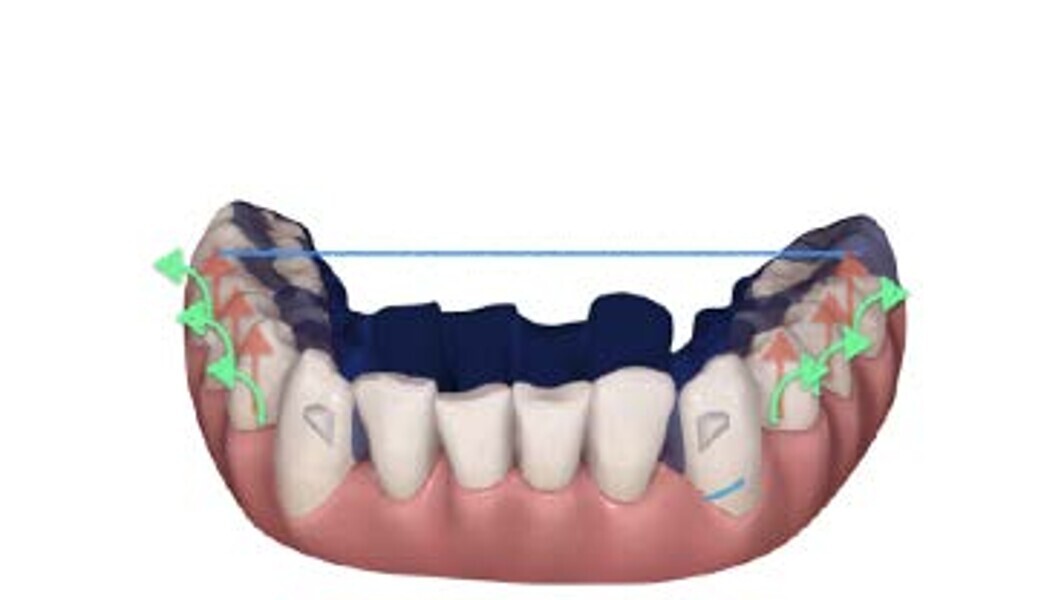

Élaboration du plan de traitement numérique

Pour bien corriger une mal-occlusion de type supraclusion au moyen d’aligneurs, Align Technology a intégré des rampes d’occlusion de précision, ainsi que des bourrelets d’occlusion (turbos) antérieurs personnalisés dans son système d’aligneurs Invisalign, et ceux-ci sont disponibles pour la face linguale des incisives centrales et latérales supérieures, ou des canines supérieures. Contrairement aux attachements classiques, ces éléments auxiliaires ne nécessitent pas l’utilisation d’une résine composite ; ils constituent une extension linguale de l’aligneur (extension palatine maximale de 3 mm) qui crée des contacts prématurés dans la région antérieure et par conséquent, une désocclusion des dents postérieures. Les rampes sont prévues pour surélever progressivement l’occlusion, ce qui accroît l’espace interocclusal postérieur nécessaire à l’extrusion relative des dents latérales et postérieures. Les rampes doivent être combinées avec deux autres types d’éléments auxiliaires : les taquets, qui sont utilisés pour l’extrusion des dents latérales, et la création de points de pression au niveau de la face linguale des incisives inférieures, qui permettent d’exercer plus efficacement des forces intrusives suivant le grand axe des incisives. Il est ainsi possible d’optimiser le nivellement de la courbe de Spee mandibulaire, en combinant deux mouvements réciproques dans deux parties différentes de l’arcade, c’est-à-dire intrusion dans la région antérieure et extrusion dans la région postérieure, comme le décrit la littérature.6, 7

Lors de l’élaboration du plan de traitement numérique (logiciel ClinCheck), il convient surtout de veiller au nivellement précis de la courbe de Spee dans les 3 dimensions :

• Dans le plan vertical, les deuxièmes molaires inférieures représentent un point de référence et ne nécessitent donc pas une extrusion, alors que ce mouvement doit être prévu pour les premières molaires, les secondes prémolaires et (parfois) les premières prémolaires (en fonction de l’importance du rayon de courbure de la courbe de Spee). L’intrusion doit être effectuée simultanément d’une canine à l’autre afin d’obtenir un recouvrement incisif normal.8

• Dans le plan sagittal, la disto-version des deuxièmes et premières molaires, combinée avec la mésioversion des prémolaires et des canines, favorise le nivellement de la courbe de Spee. Ce mouvement est synergique et la disto-version favorise partiellement l’extrusion des molaires.

• Dans le plan transversal, le redressement des prémolaires et des molaires pour parvenir à un torque proche de 0 degré, induit une extrusion relative des segments latéraux et contribue au nivellement de la courbe de Spee, ainsi qu’à des contacts occlusaux postérieurs prématurés.9

Dans la planification numérique, le degré d’extrusion postérieure planifié en 3D crée de puissants contacts occlusaux sur les cuspides d’appui, et ces contacts prématurés permettent une intercuspidation cliniquement appropriée, sans perte des contacts occlusaux durant le traitement, ce qui entraîne une rotation de la mandibule dans le sens horaire. Enfin, pour faciliter la rotation mandibulaire et l’intercuspidation, des élastiques de classe II, dont la composante verticale de la force est directement reliée aux aligneurs, seront utiles pour obtenir une extrusion absolue et relative.